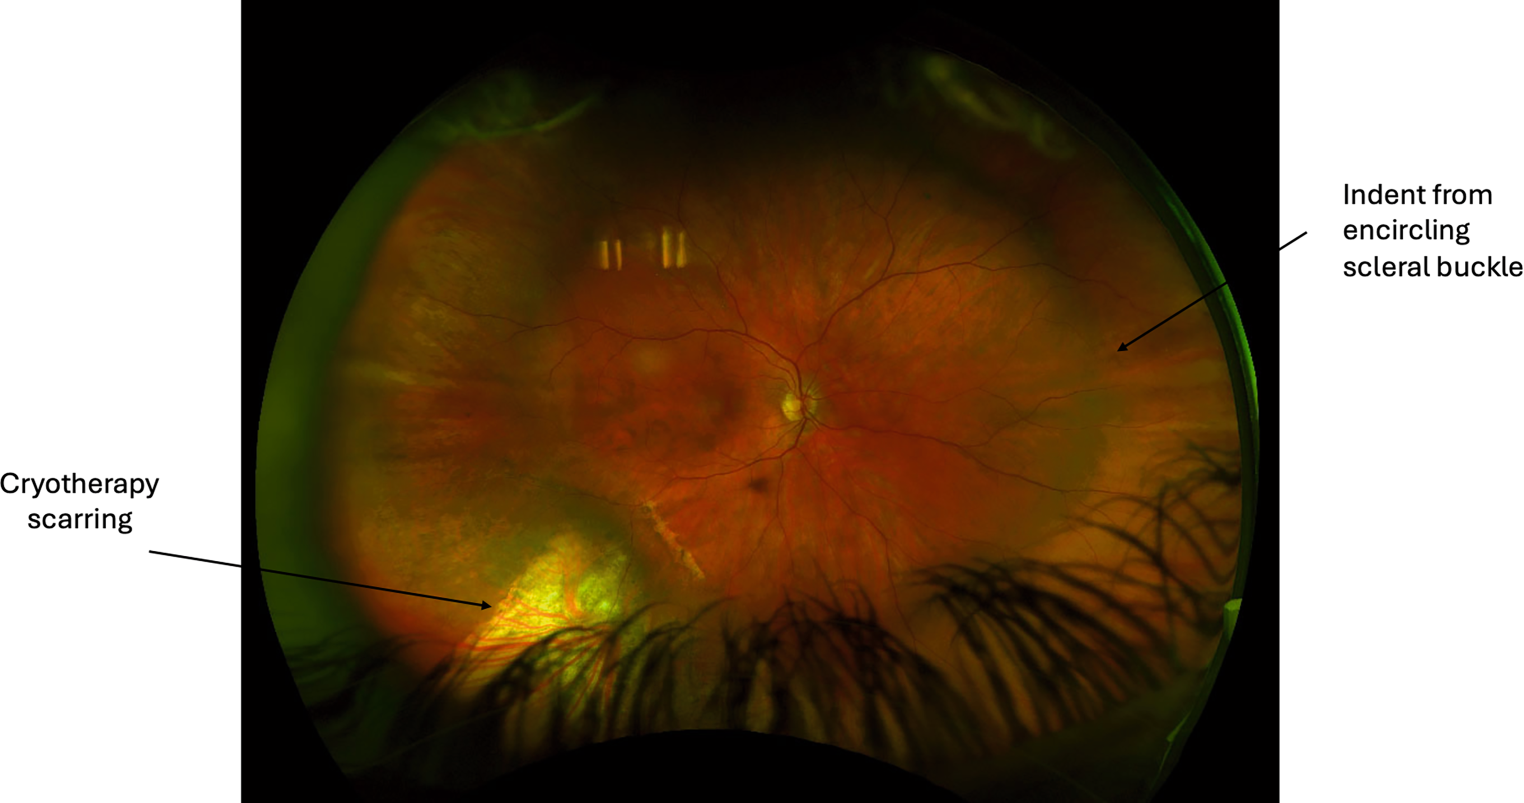

Fig. 8

Reattached retina after scleral buckle surgery with cryotherapy

Proliferative vitreoretinopathy

The pathophysiology of proliferative vitreoretinopathy (PVR) has been extensively studied, with resultant formation of contractile proliferative cellular membranes on both the vitreous cavity and the retina [85]. Contraction of these membranes and intraretinal fibrosis can cause the retina to re-detach and fail to flatten. It is the most common cause of retinal detachment repair failure, with an incidence of 5–10% among all cases of RRD [86, 87]. Proliferative vitreoretinopathy grading was first recognised by The Retina Society Terminology Committee in 1983 and then updated in 1991 [86, 88, 89]. Grade A PVR was defined as the presence of vitreous haze and pigment clumps. Grade B PVR involves retinal wrinkling, rolled edges of the retinal break with retinal stiffness and vessel tortuosity. Grade C involves full-thickness retinal folds and/or subretinal bands and pathologic changes that can occur anteriorly, posteriorly or both. Grade C PVR was further differentiated into types 1–5, depending on the location of proliferation, type of contraction and extent in clock hours ([86, 89]; Fig. 3).